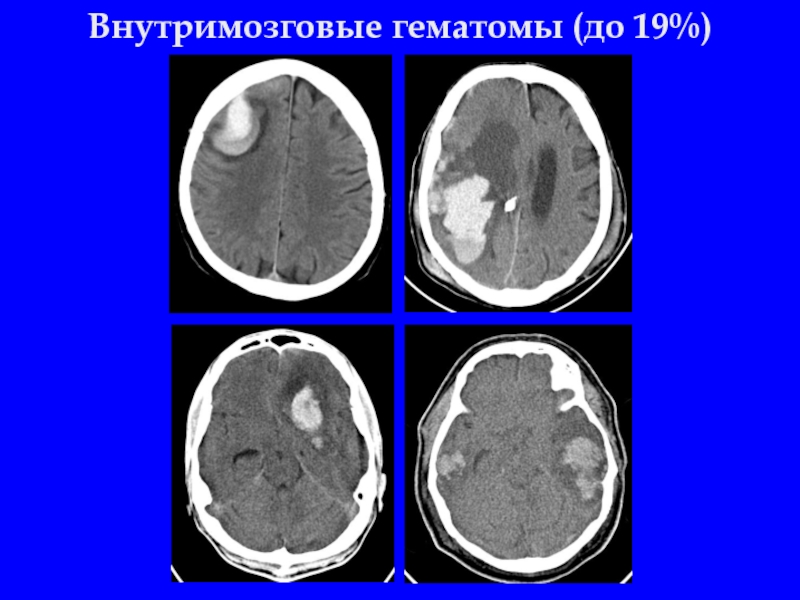

Слайд 19Внутримозговые гематомы (до 19%)

Слайд 20Внутримозговая гематома

Линейный перелом слева, отёк, латеральная дислокация